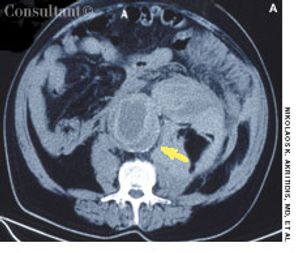

Severe abdominal pain radiating to the back prompted a 72-year-old man to go to the emergency department (ED). The patient had experienced similar pain 2 days earlier and was treated at another hospital for renal colic on the basis of concomitant microscopic hematuria. He had a history of poorly controlled hypertension.